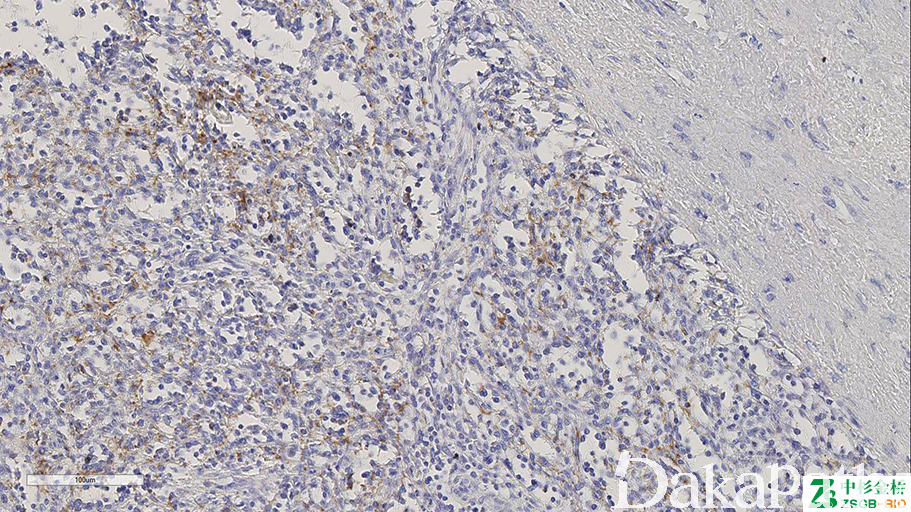

CD61

别名: integrin beta 3 chain (ITGB3)、GPIIIa

与 CD41 结合形成血小板糖蛋白 Iib/IIIa 复合体,参与凝血及血栓形成。骨髓巨核细胞及血小板的标记物,也可标记髓系、内皮细胞等。对过度脱钙敏感,可以作为脱钙程度的内参。

信号定位: 胞膜、胞浆